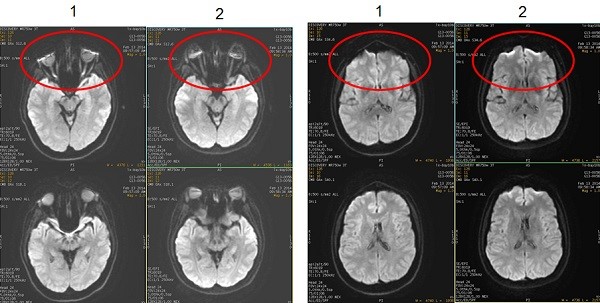

Restricted diffusion

The extra-cellular water in normal brain tissue diffuses freely, resulting in a dark signal. The extra-cellular water in dead brain tissue does not diffuse, resulting in a bright signal.

Figure 11. Normal vs. restricted diffusion

Table 6. Image legend

NumberDescription

1Normal diffusion

2Restricted diffusion